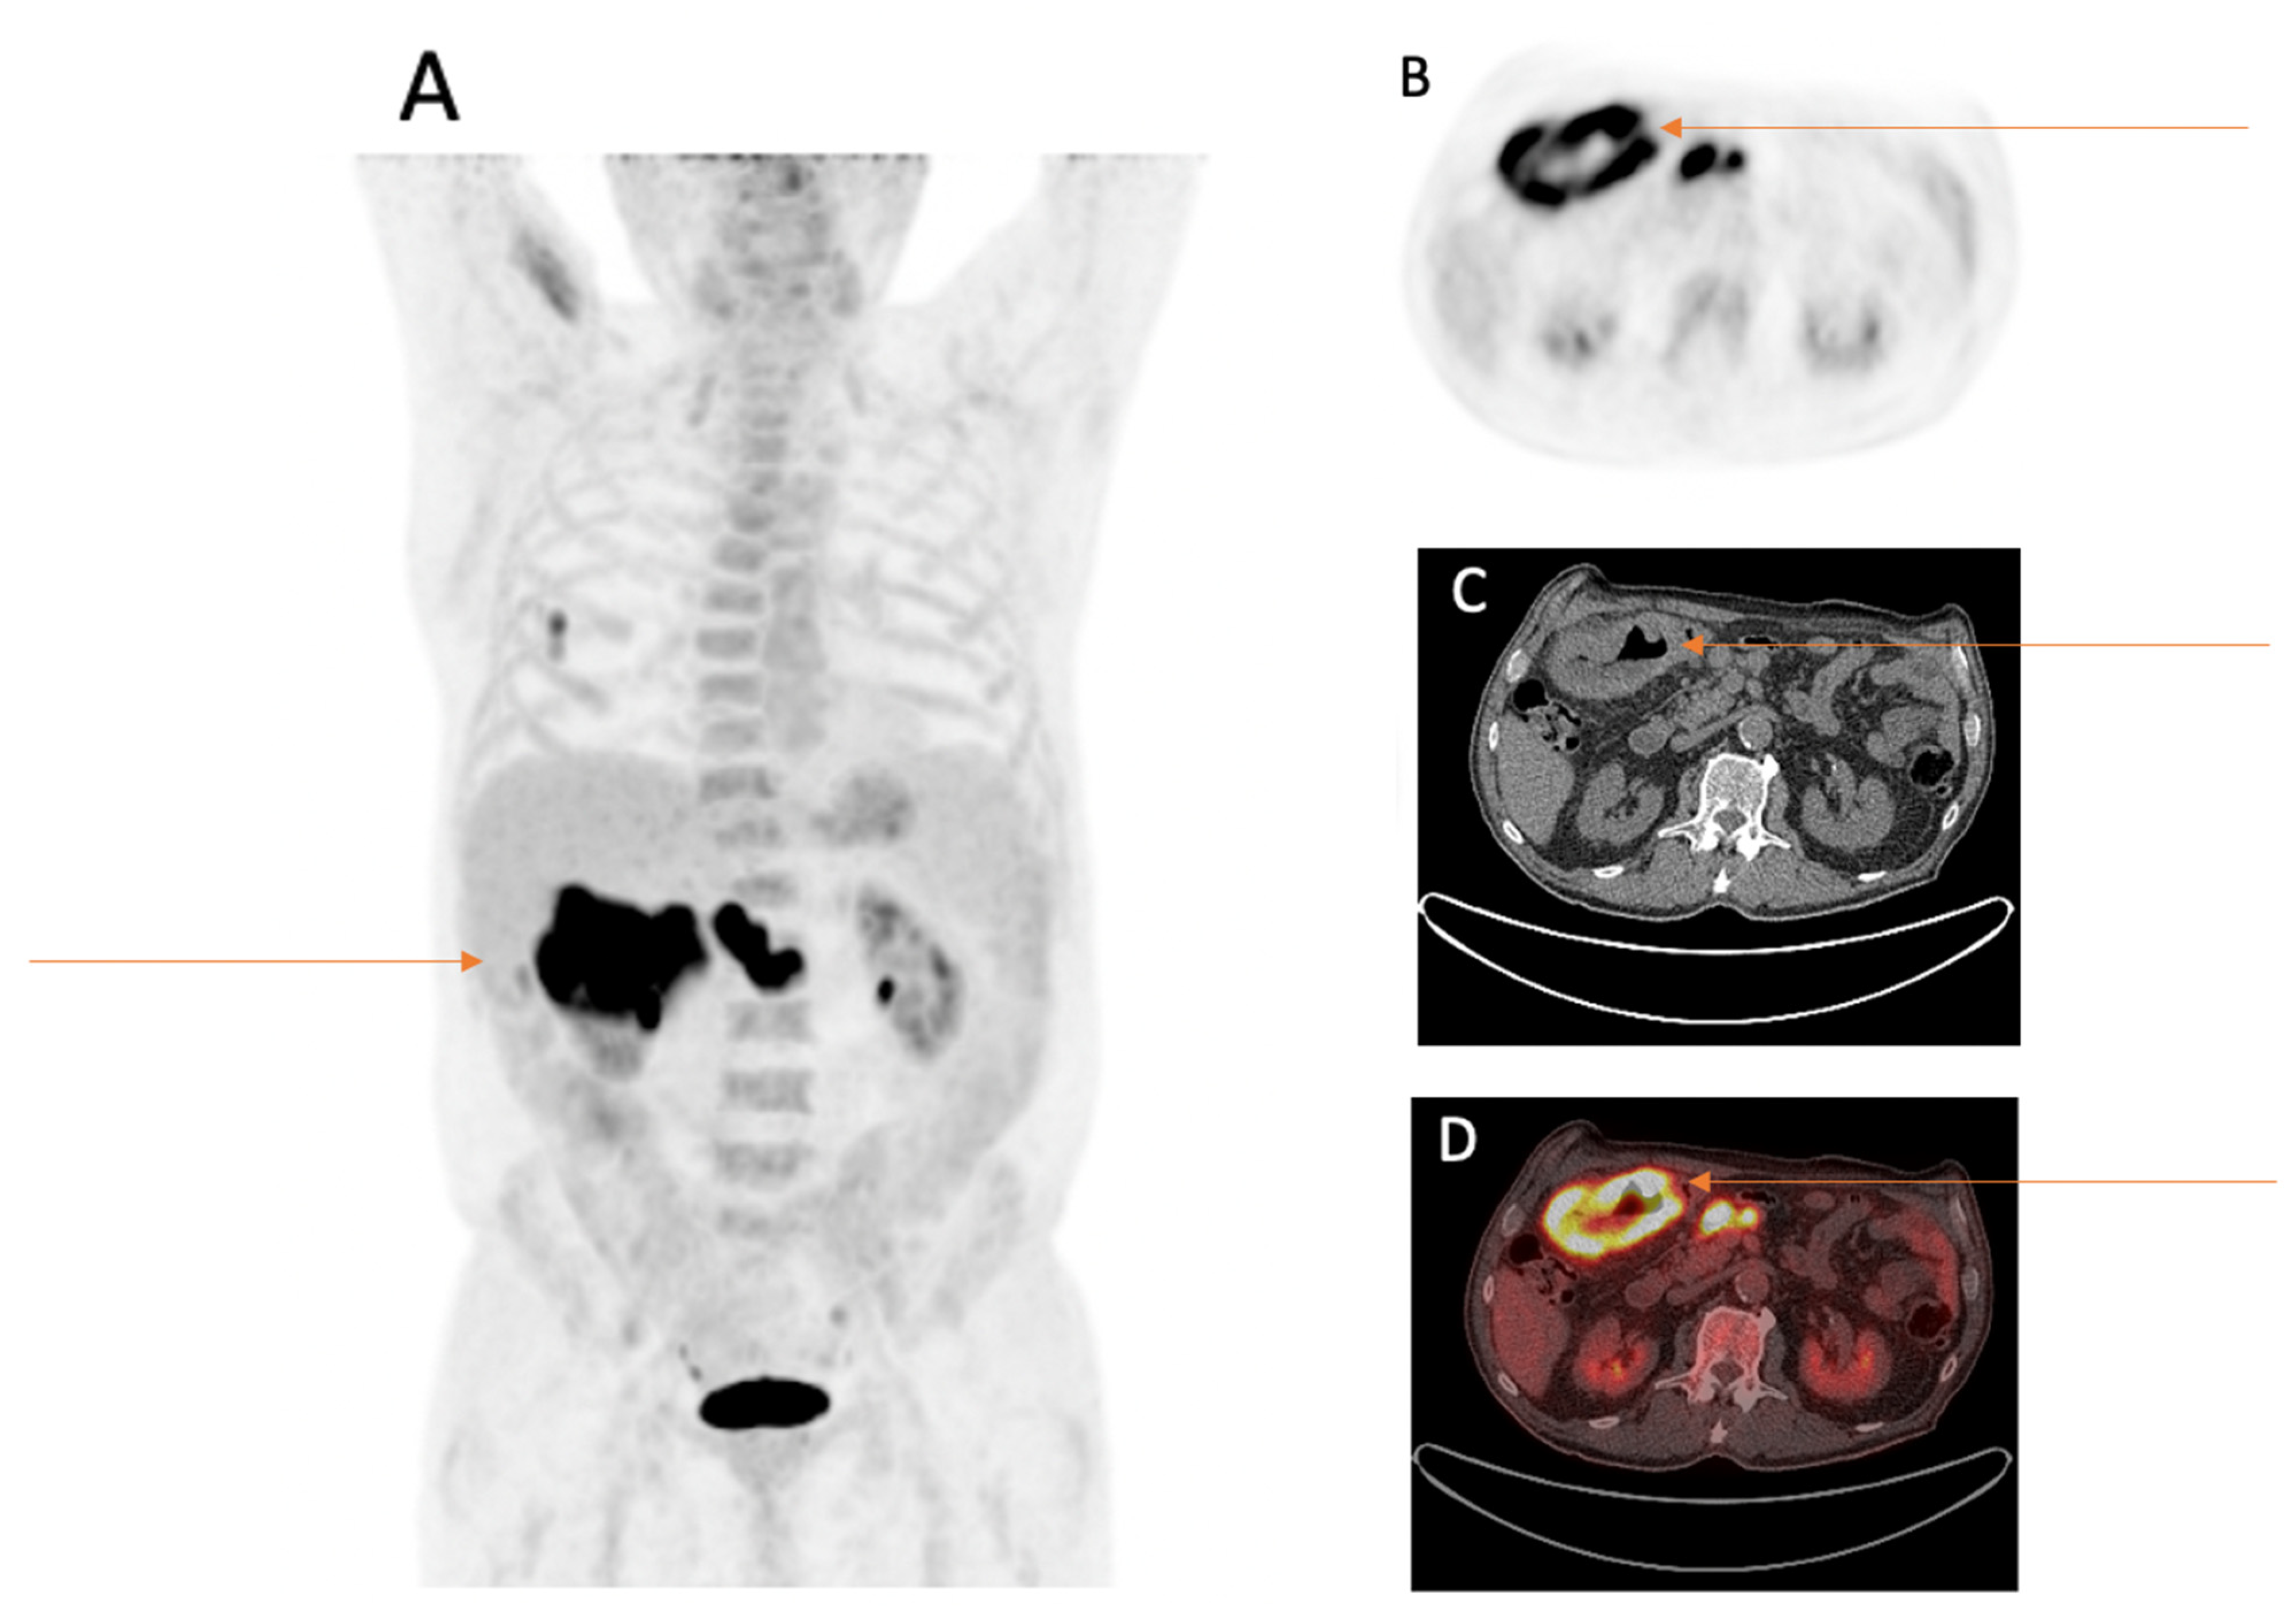

Additional Primary Tumors Detected Incidentally on FDG PET/CT at Staging in Patients with First Diagnosis of NSCLC: Frequency, Impact on Patient Management and Survival

3.4. Further Description of Suspicious Findings